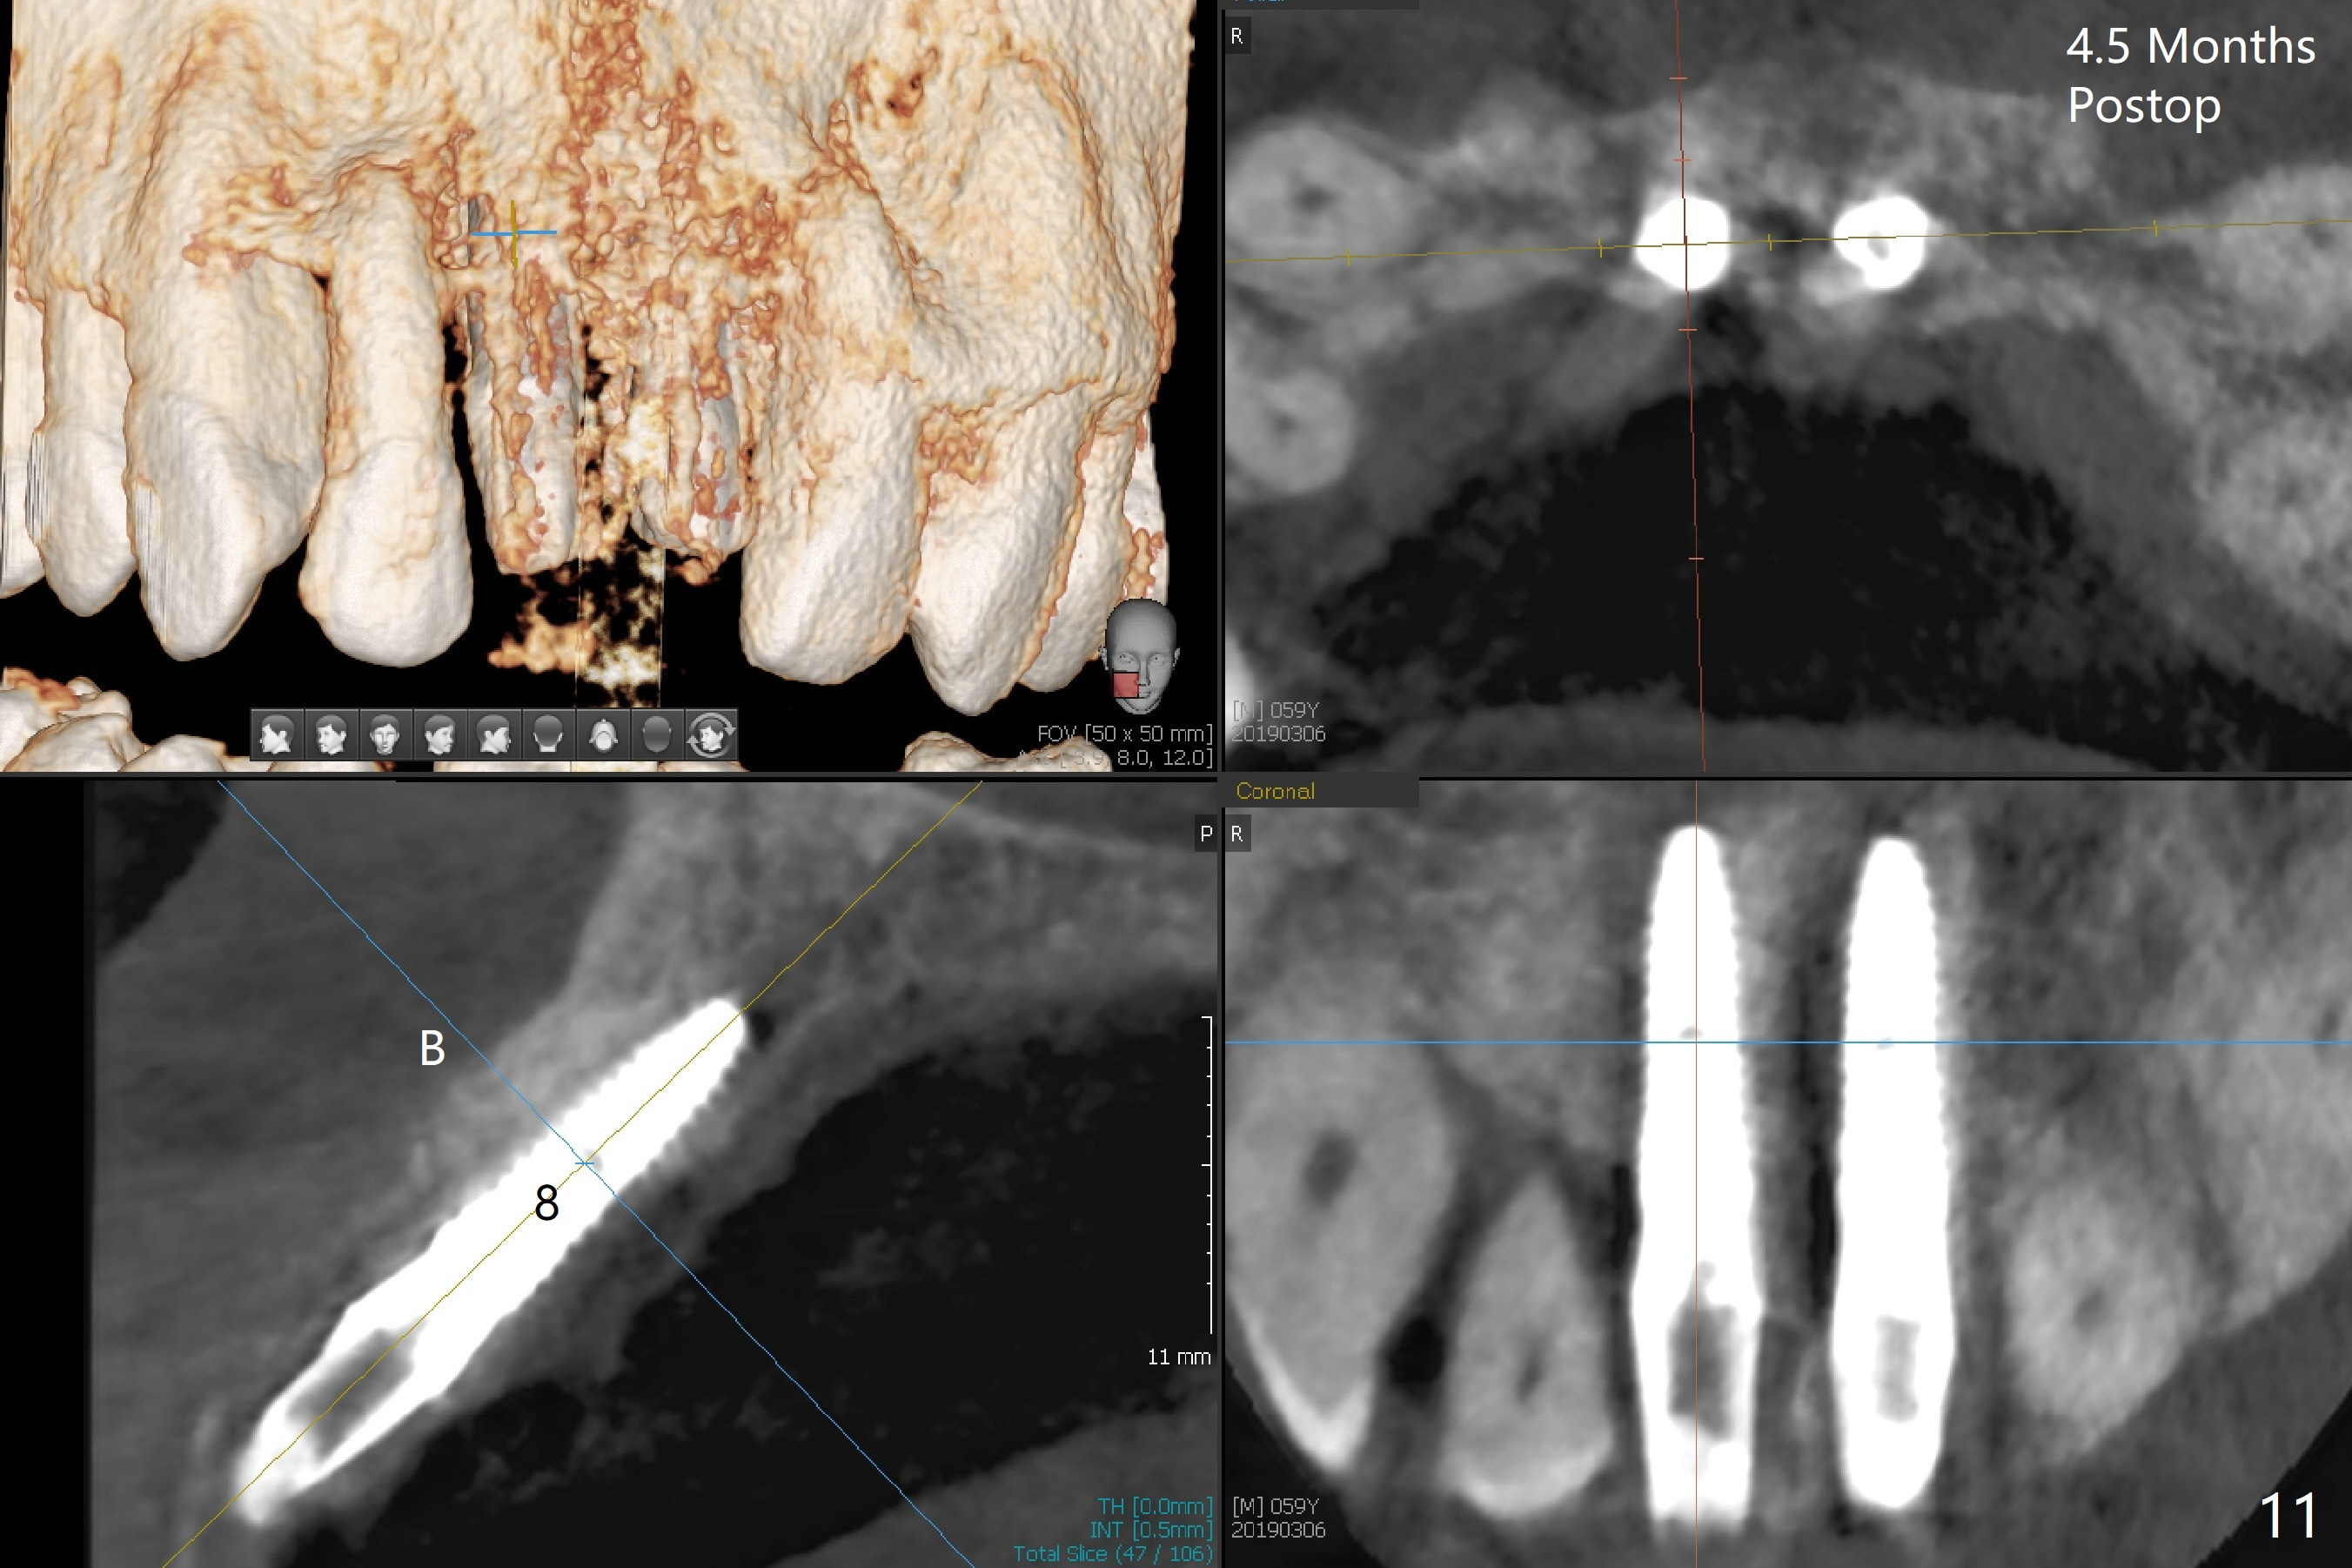

There is no buccal plate at #8 or 9 when the teeth are extracted as well as severe soft tissue defect at #8. Osteotomy is initiated as palatal as possible (Fig.1). When 3.5x13 mm implants are placed initially, the one at #8 is supracrestal (Fig.2 ^). To reduce the chance of peri-implantitis, the implant is placed deeper (Fig.3 (~2 mm implant threads exposed buccally)) with placement of sticky bone around the implants and 4.5x5.5(4) mm abutments (Fig.3 *). The buccal soft tissue defect #8 is repaired with a piece of PRF membrane (Fig.4 *), followed by periodontal dressing. Smaller 2-piece implants (3 mm, IBS) with smaller abutments (4 mm) may further reduce chance of periimplantitis and easy buccopalatal reduction of the abutments for restoration. The periodontal dressing remains stable 7 days postop (Fig.5) because it wraps around the abutments (Fig.6 A). By the time the periodontal dressing gets loose, #8 buccal soft tissue defect should be healing. When breaking-down periodontal dressing is removed 17 days postop, the coronal abutments and bone graft are exposed; after fabrication of provisional crowns (Fig.7), periodontal dressing is re-applied buccally. When the second dressing dislodges 5 weeks postop, the buccal soft tissue appears to reduce (Fig.8). Raising flaps may be less traumatic. A piece of bone graft is being extruded 4 months postop (Fig.9 >). After the abutments change from 4.5x5.5(4) to 4.5x7(3) mm, new temporary crowns are fabricated (Fig.10 (4.5 months postop)). CT shows apparent buccal bone at #8 and 9 (Fig.11,12). How to improve cosmetic?